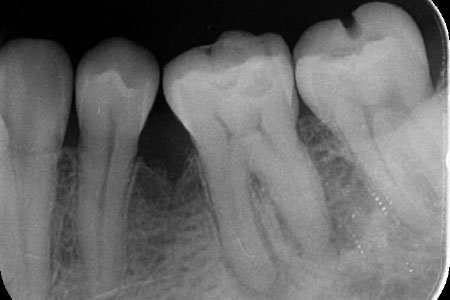

肉眼で診るとそんな問題なさそうにみえます。

マイクロスコープでみて、根管をきれいにすると両方の根管から出血が認められ、根管の穿孔が確認できます。

根管の穿孔してる部位周辺をきれいにしています。穿孔部からは出血を伴いますのでなるべく穿孔部には触れず、そのまわりをきれいにする繊細な処置です。マイクロスコープが活躍します。

きれいにした状態です。穿孔部がはっきりと確認でき、あまり出血していない状態です。

穿孔部の封鎖です。穿孔部の出血や浸出液をコントロールして充填していきます。

根管上部が穿孔部位なのでしっかり充填できてるのがわかります。今後腫脹や痛み等症状がなくなったのを確認して、最終的な補綴物に移行していきます。

| 主訴 | 違和感がとれない |

根管治療、 穿孔封鎖 |

| 治療期間 | 2ヶ月 |

| 治療費 | ¥80,000 |

| 治療のリスク | 治療開始して根管を診てみると、予測したより重症で治療しても症状が改善しない場合がある。最悪の場合抜歯になる可能性がある。 |